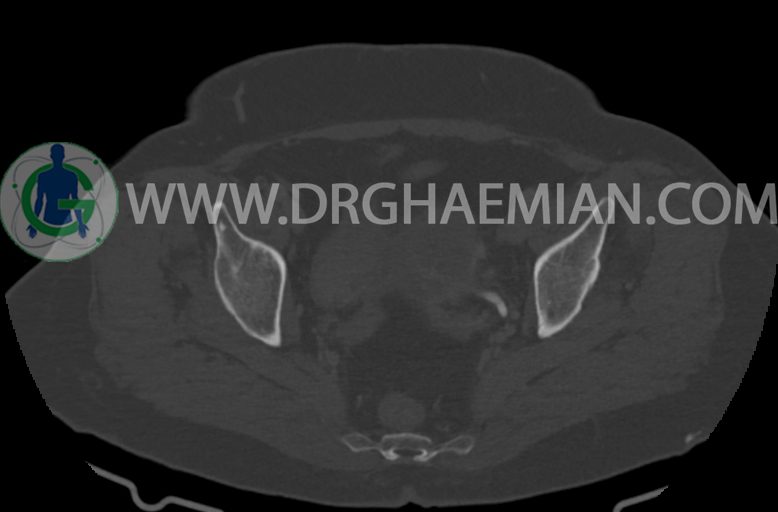

سی تی اسکن شکم و لگن با استفاده از اشعات ایکس تصاویر عرضی از ناحیه شکم و لگن ایجاد میکند. در این کیس موسینوس کیست آدنوما، شواهد هیسترکتومی، ضایعه در سمت راست لگن، کیست در کبد و … دیده می شود.

–شواهد هیسترکتومی

–تغییرات DJD در L5/S1

مشهود است.